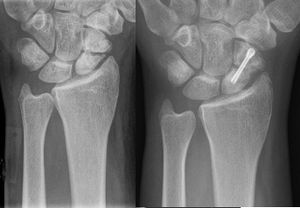

Scaphoid fracture

- Most commonly fractured carpal bone

- Most common fracture at the waist of the scaphoid

- X-ray

- Obtain both standard and scaphoid views

- Up to 10% of initial radiographs fail to detect a fracture